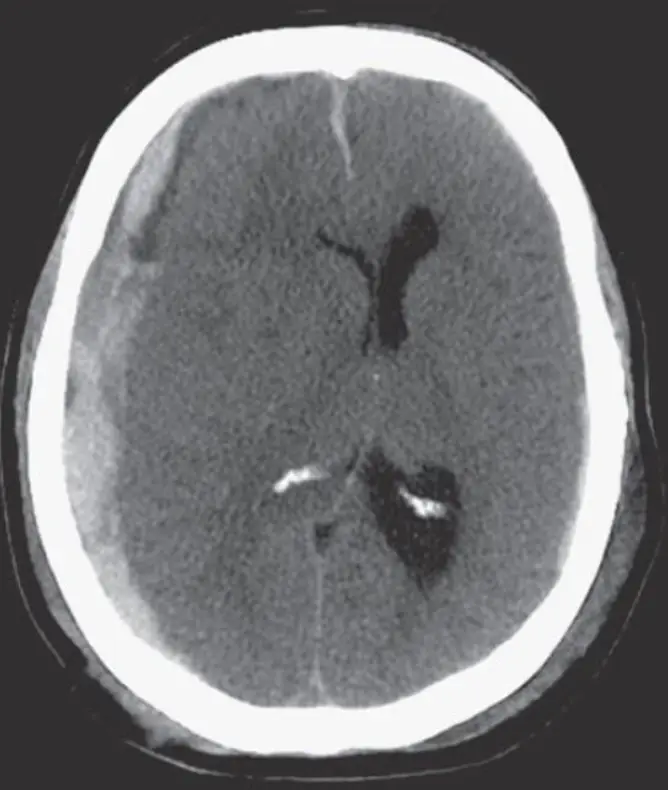

一位摩托車車禍病人送至醫院,其電腦斷層顯示如圖(五),下列敘述何者最適當?

從所給的 axial non-contrast CT 片觀察到:

- 血塊位在大腦凸面 (cerebral convexity) 之下,呈新月形 (crescent-shaped) 高密度積血,且可跨越顱骨縫線 (suture lines);

- 大量血腫造成顱內壓力上升,明顯向對側推擠中線結構 (midline shift),並壓迫鄰近腦室與腦溝;

- 血腫質地均勻高密度,符合急性新鮮血塊 (acute blood clots) 的表現;

此種典型圖像符合急性硬腦膜下血腫。